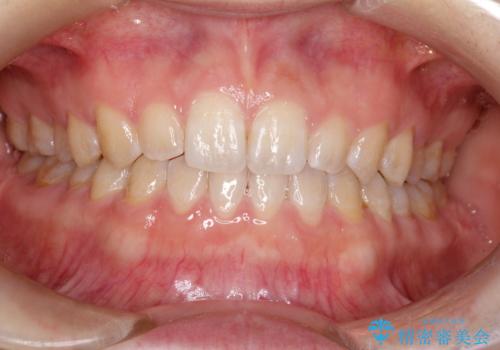

前歯の隙間を閉じたい インビザラインによる矯正

- 上下の前歯に隙間があるとのことで来院されました。

インビザラインにて隙間を閉じる矯正を行いました。

使用時間を守っていただけたので、比較的スムーズに矯正を終了することができました。